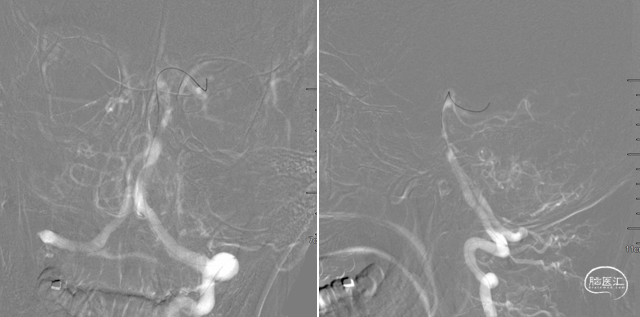

支架后造影

最后造影